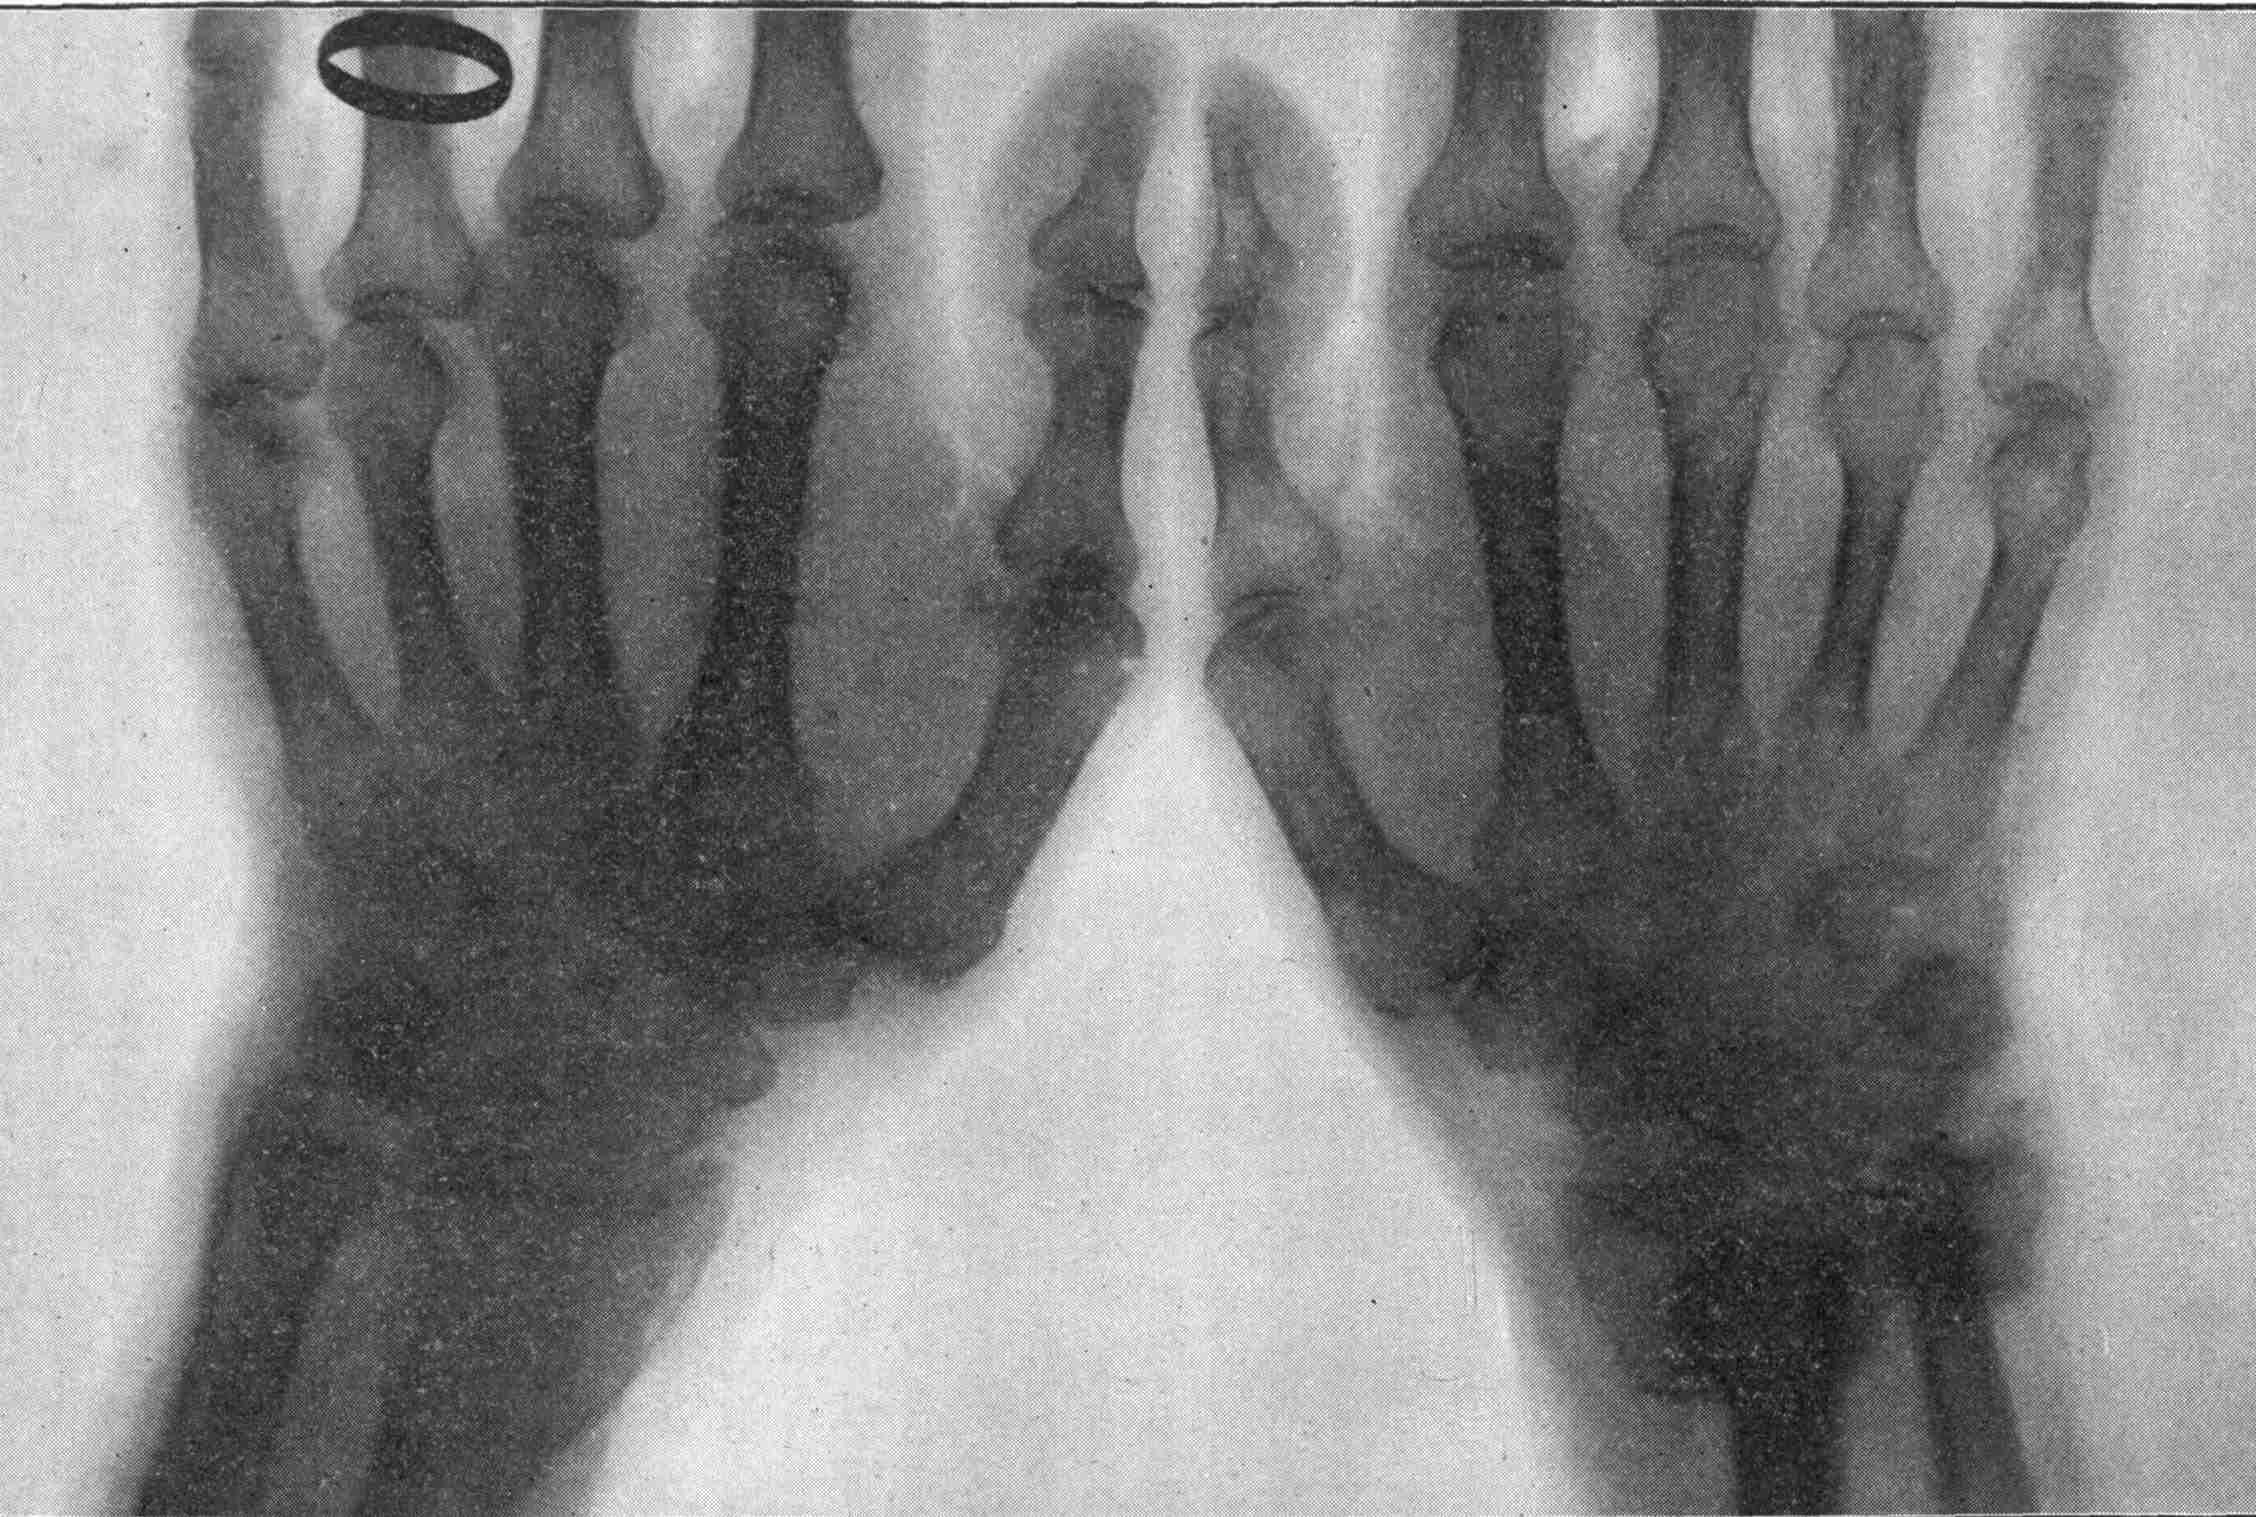

Fig. 3.—Ribs.

FROM SCIAGRAPHS BY PROF. DAYTON C. MILLER. § 204.